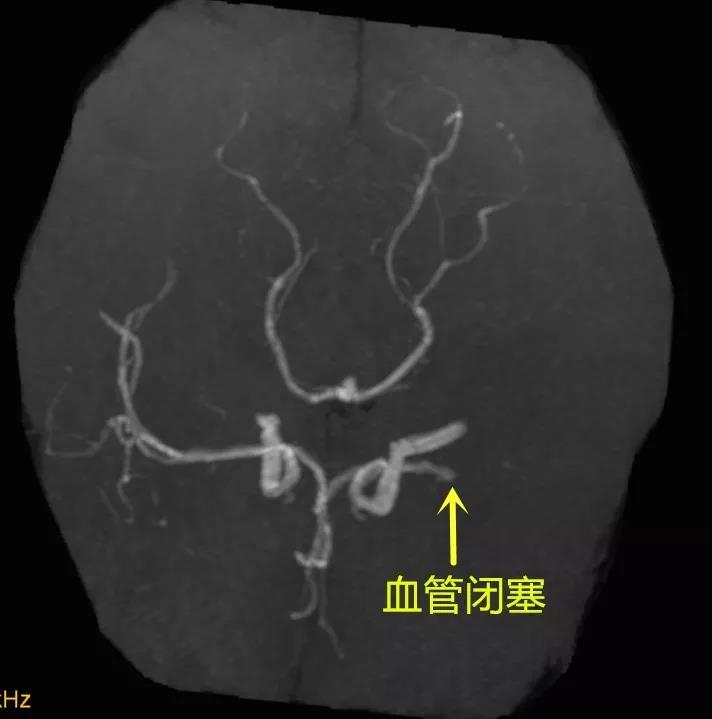

2019年4月18日,37岁的李女士在上班时突然出现了言语不清、右侧肢体瘫痪的症状,随即被送至桓台县人民医院急诊科,行颅脑CT检查诊断为脑梗死。因李女士有心脏病史,一直服用抗凝药,无法进行静脉溶栓治疗,接诊医生立即请卒中小组会诊,神经内科三病区王克水主任查看患者后,考虑患者是左侧大脑血管堵塞,紧急磁共振血管成像检查证实了王主任的判断。

磁共振血管成像

对于急性脑梗死的患者来说,时间就是生命,在“时间窗”内经行溶栓或者介入取栓治疗,对患者的恢复至关重要,如果超出这个“时间窗”,患者可能会遗留终身残疾,甚至有生命危险。李女士病情危重,需要行急症介入取栓治疗。